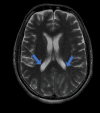

Figure 3

Figure 3. MRI brain showing few areas of diffusion restriction which were of high intensity on DWI sequence predominantly on the left side with gyriform pattern

DWI: diffusion-weighted imaging